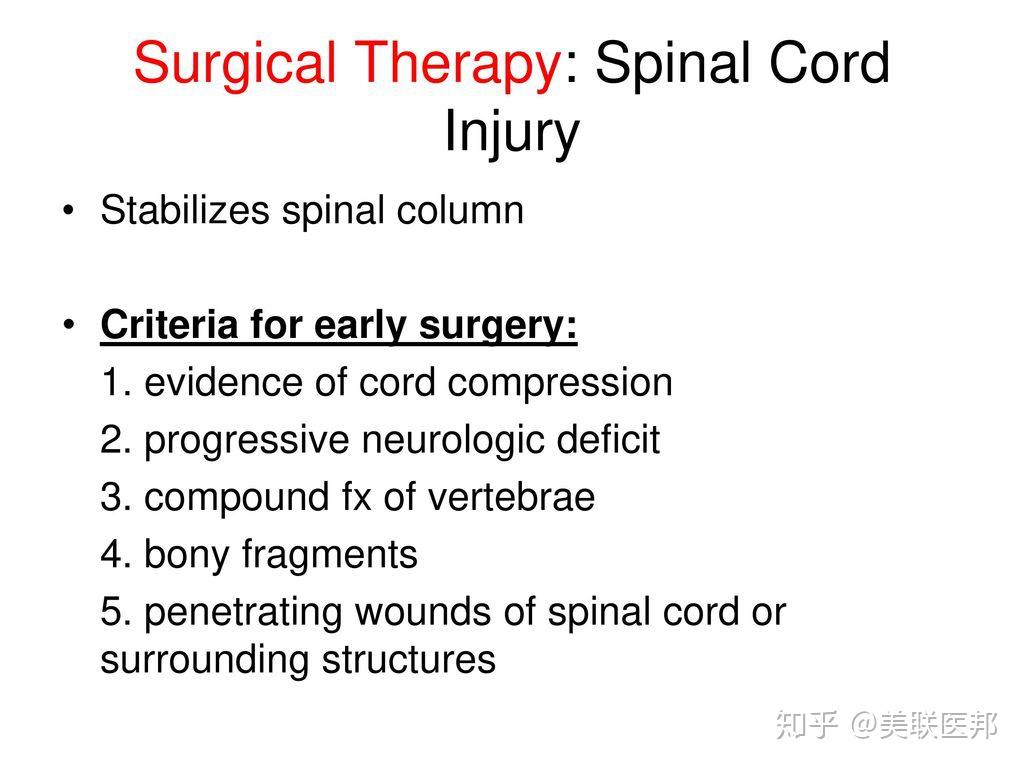

手术:通常需要手术来移除看上去压迫脊柱的骨头、异物、突出的椎间盘或骨折的椎体。也可能需要手术来稳定脊柱以防止将来出现疼痛或畸形。